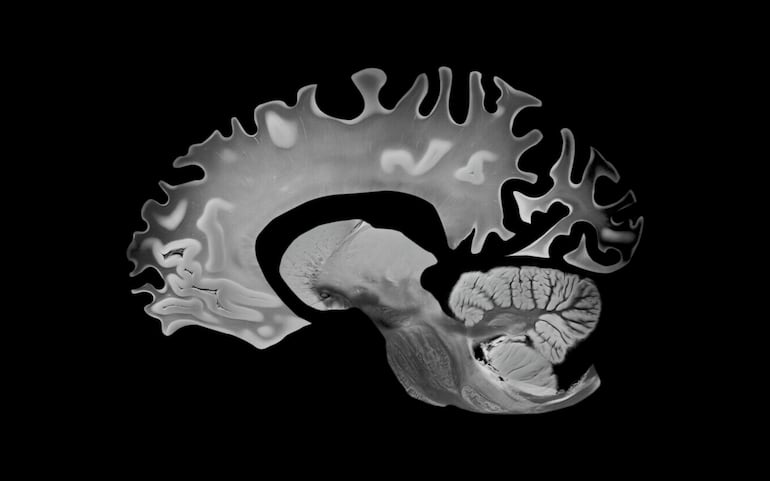

La confirmación absoluta sigue siendo anatomopatológica, pero hoy existen evaluaciones clínicas y neuropsicológicas, neuroimagen (RM, PET) y biomarcadores en líquido cefalorraquídeo—e incluso pruebas sanguíneas emergentes—que ofrecen alta precisión diagnóstica.